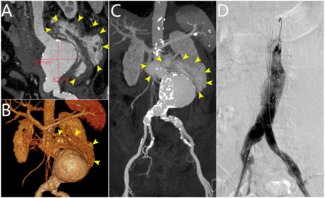

A 72-year-old woman presented with acute onset of abdominal pain accompanied by nausea and vomiting for 10 hours. Computed tomography angiography revealed a ruptured abdominal aortic aneurysm with extensive intraperitoneal hemorrhage.